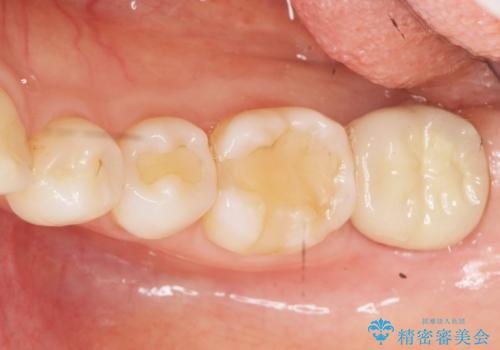

- 昔何回か根管治療した奥歯が膿んでいていて痛みがあることを主訴に来院された患者様です。

精査したところ、左下の奥歯にはひびが入っていて、保存不可能な状態でした。

義歯・インプラント・親知らずの移植の選択肢を提案したところ、移植をご希望されました。

割れている奥歯を抜去後左上の機能していない親知らずを移植し、生着したのち根管治療・補綴を行いました。